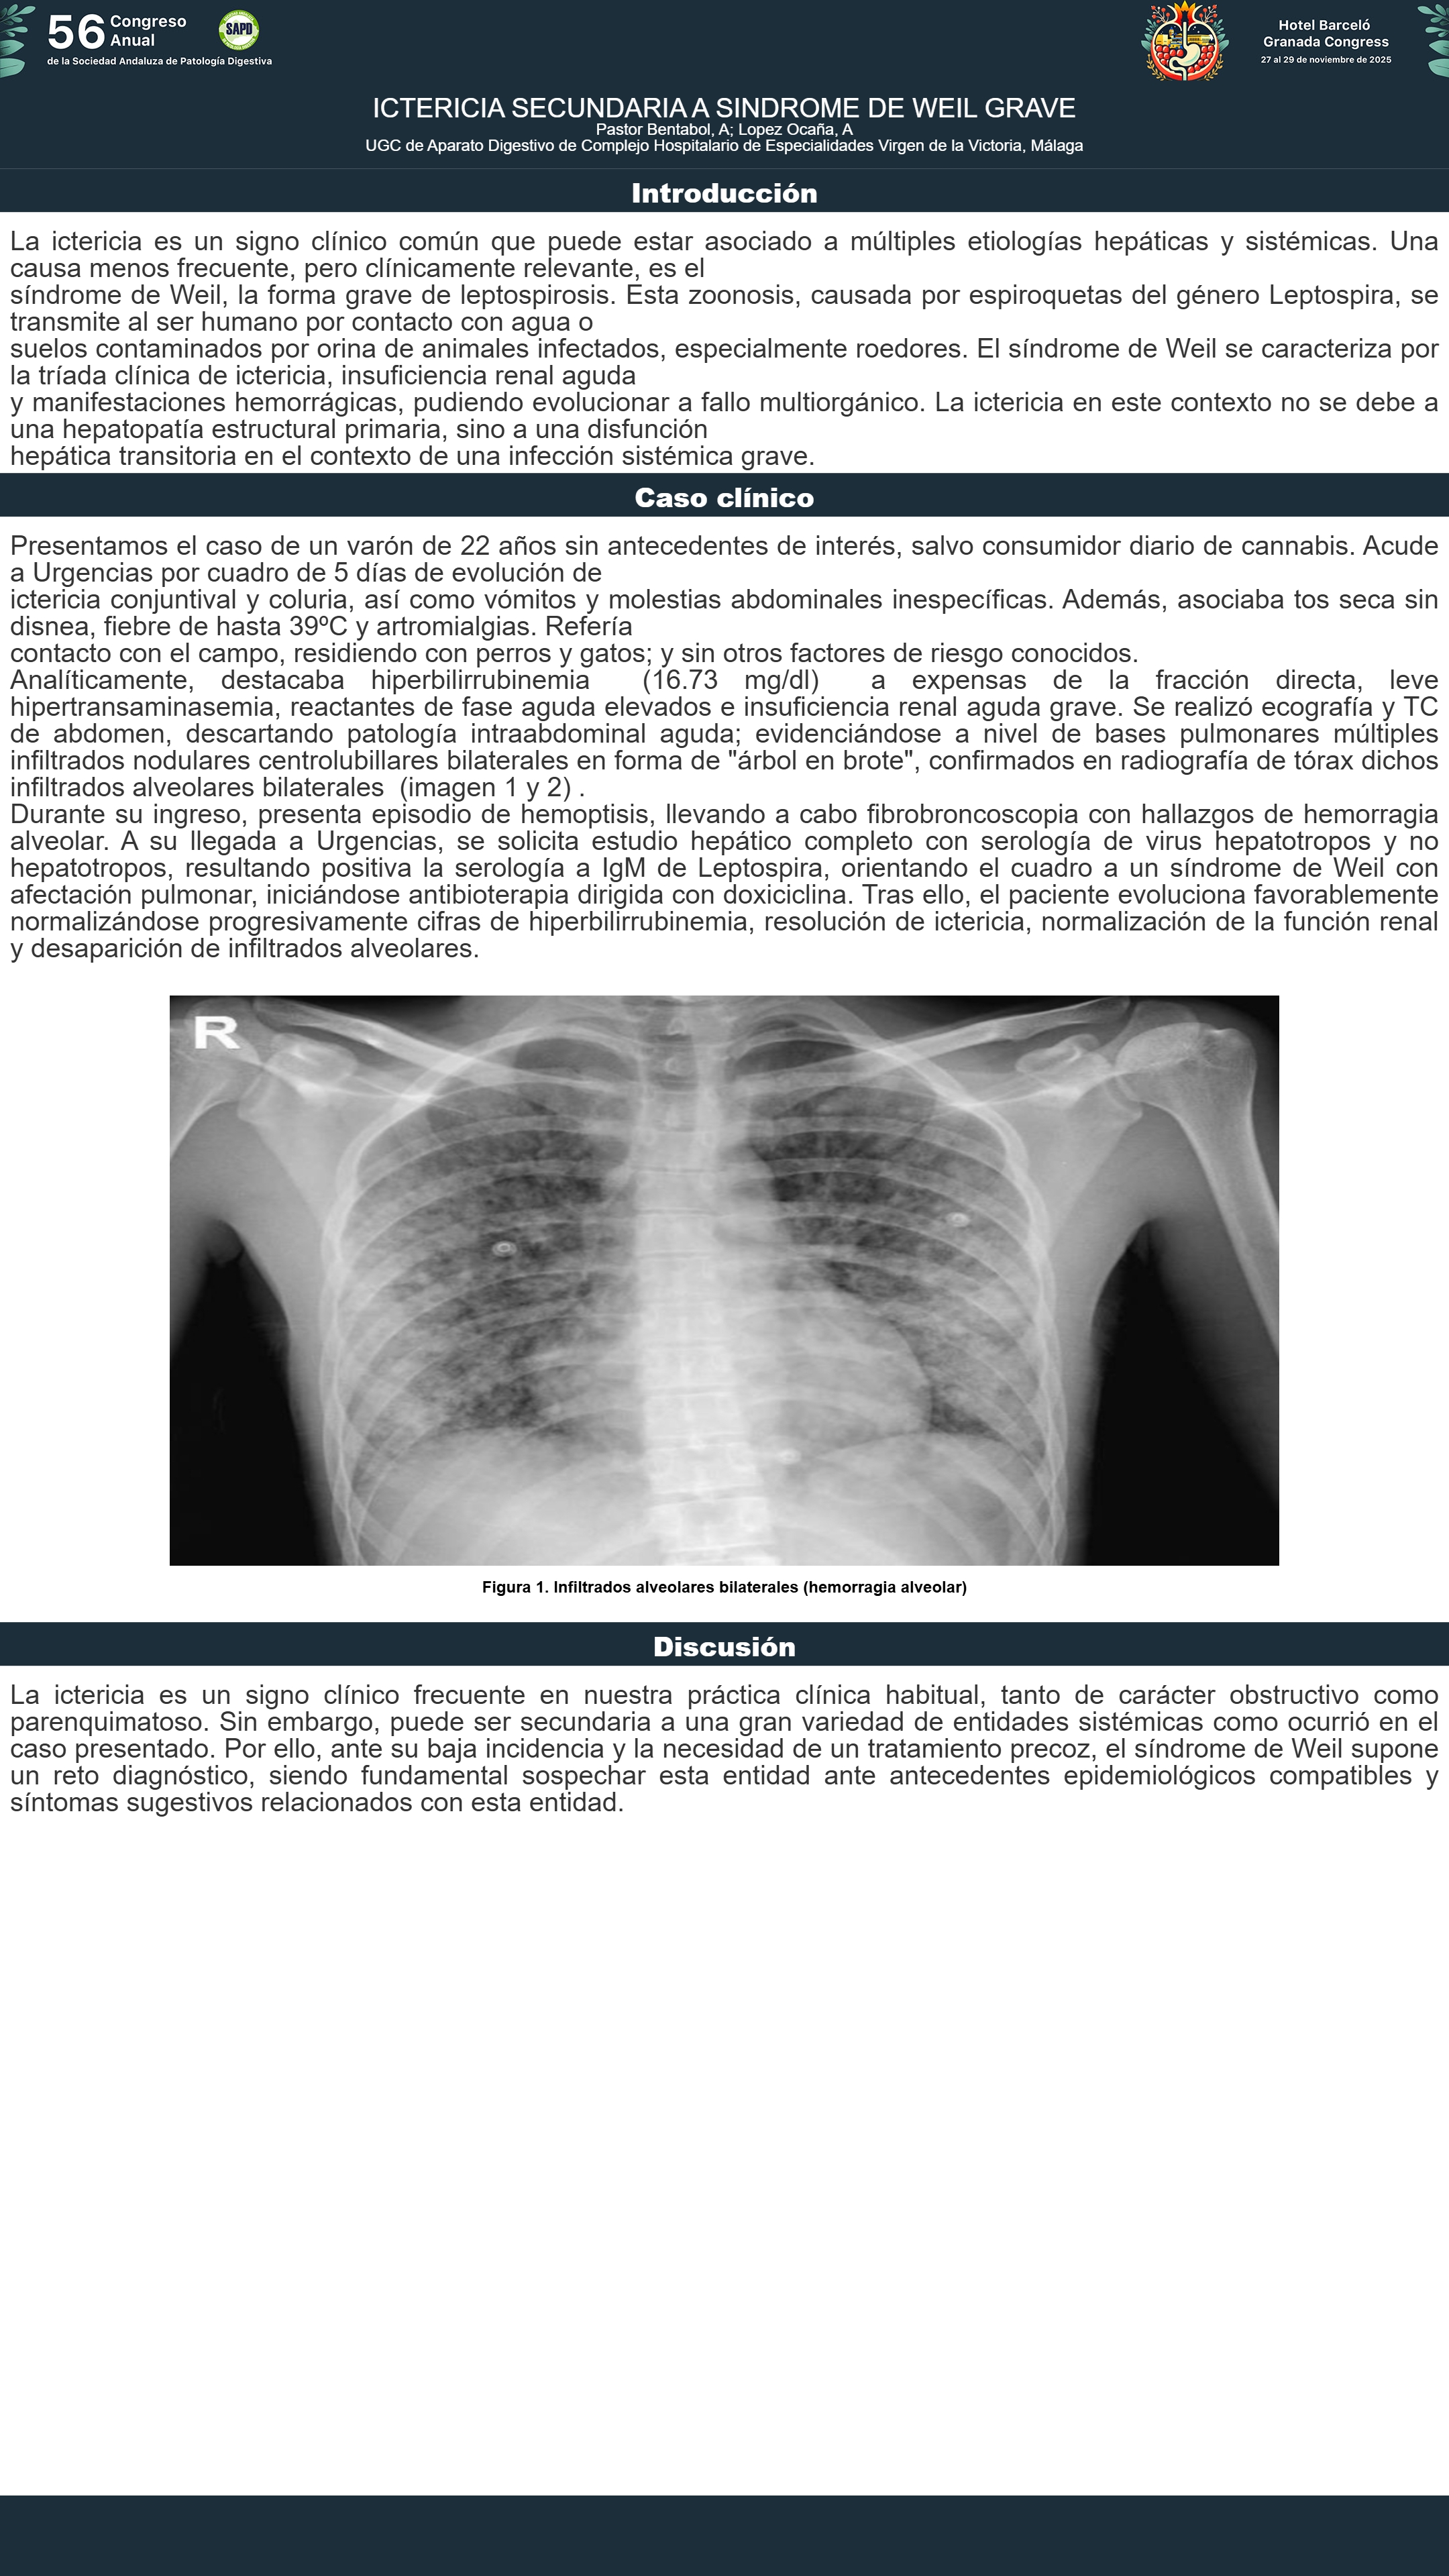

[CP-061] ICTERICIA SECUNDARIA A SINDROME DE WEIL GRAVE